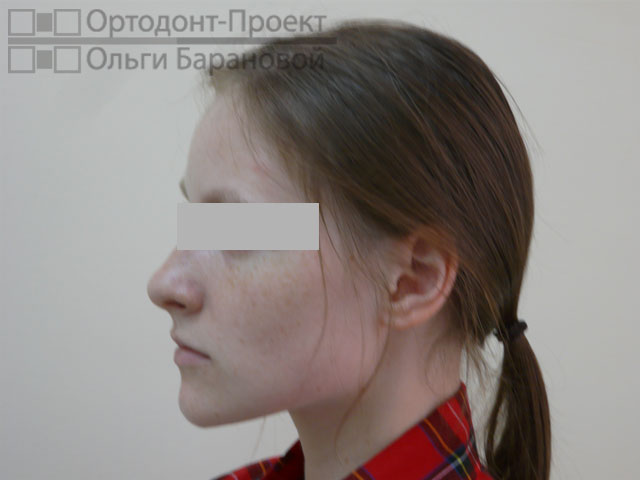

Проблема: к ортодонту О.А. Барановой обратилась молодая девушка с жалобами на то, что криво растут зубы.

Решение: выполнено лечение с удалением зубов, наиболее эффективное в данном случае. Для лечения использованы металлические брекеты Damon.

Ортодонт О.А. Баранова провела осмотр и рассказала о возможностях ортодонтического лечения. Возможны два варианта лечения при скученности зубов – с удалением или без удаления зубов. В «ОРТОДОНТ-ПРОЕКТЕ Ольги Барановой» редко используется удаление зубов, но в данном случае, при сильной скученности зубов и тонком биотипе пародонтальных тканей, у девушки ещё есть полноценные «восьмерки», поэтому все признаки за лечение с удалением. В данном случае лечение с удалением зубов приведёт к максимально грамотному, эстетичному и стабильному результату.

Фотометрия перед ортодонтическим лечением:

Вторая причина — протрузия (выступание передних зубов). Зубы обеспечивают поддержку мягких тканей — щек, губ. При выраженном наклоне передних зубов мы часто наблюдаем «выпуклый» профиль. Иногда пациенту даже сложно сомкнуть губы. Удаление зубов в данном случае является абсолютно оправданной мерой для изменения положения зубов и улучшения эстетики лица.